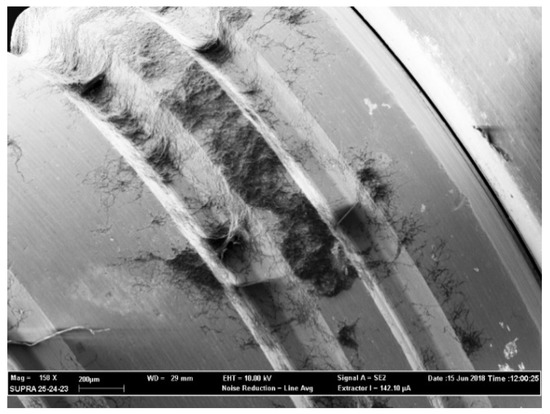

4.4. SEM Observation